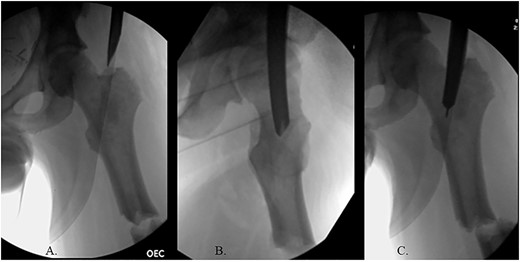

The patient was positioned supine on a fracture table. A guide wire was inserted through a 4-cm surgical incision proximal to the greater trochanter (GT) and was passed through a cannulated awl in a position slightly medial to the tip of the GT on the AP and center on the lateral (Fig. 2B). A (15-mm) entry reamer widened the opening (Fig. 2C). A rigid cannulated reduction rod and forceful malleting allowed the ball-tipped guidewire to cross the close reduced fracture, but too lateral and posterior distally (Fig. 3A and B). The cannulated flexible reamers encountered impassible blastic lesions within the proximal femur (Figs 3C and 5B).

(A) Cannulated awl positioned medial to tip of GT on the AP XR; (B) cannulated awl positioned center of GT on the lateral XR; (C) entry reamer over guide pin on the AP XR.